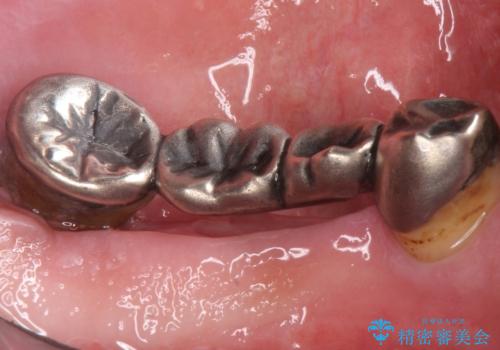

精査したところ、全顎的な重度の歯周病により左下のブリッジ(左下④56⑦)の著しい動揺を認めました。

禁煙指導と歯周病治療後、左下臼歯部(左下467埋入)のインプラント治療を行いました。